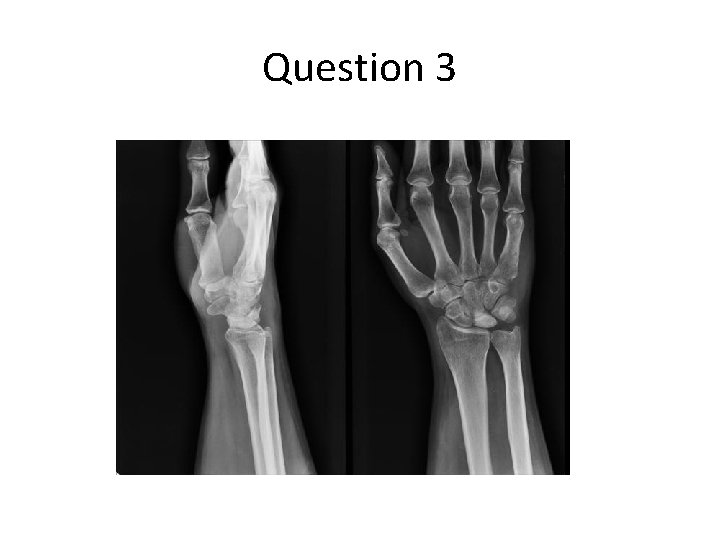

Question 3 60/M, good past health Manual worker Attended A&E for R wrist pain for 2 years He had history of repeated minor R wrist injury by spraining in the past • P/E showed R wrist swelling, stiffness and decreased ROM • X ray was taken • •

Question 3 Describe the X ray findings. • Sclerosis and hyperdensity over the lunate What is the diagnosis? • Kienböck's disease What is the cause of the above diagnosis? • Progressive collapse of the lunate • Disruption of the blood supply, possibly related to undiagnosed fractures of the lunate, repetitive trauma, or abnormal biomechanical loading patterns at the radiocarpal joint • Eventual avascular necrosis of lunate

Question 3 What are the classical X ray findings of the above diagnosis? • stage I : normal radiograph • stage II : increased radiodensity of lunate with possible decrease of lunate height on radial side only • stage IIIa : lunate collapse, no scaphoid rotation • stage IIIb : lunate collapse, fixed scaphoid rotation • stage IV : degenerative changes around lunate What other investigations can be performed to confirm the diagnosis in early stage? • Bone scan, MRI